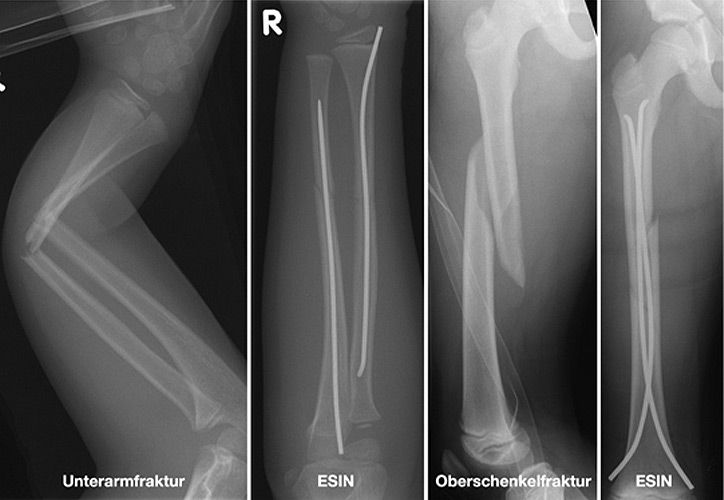

Einige Frakturen müssen auf Grund ihrer Achsabweichung operiert werden. In einer Narkose wird die Fraktur eingerichtet und ggf. mit Metall stabilisiert. Dazu stehen eine Reihe von Methoden (Osteosynthesen) zur Verfügung, die speziell für Kinder entwickelt wurden, um Wachstumsfugen zu schonen und nicht zu verletzen: Die ESIN (elastisch stabile intramedulläre Nagelung) hat sich als minimal invasives Standardverfahren zur Stabilisierung von Schaftfrakturen der großen Röhrenknochen (Unterarm, Oberarm, Unterschenkel, Oberschenkel) etabliert. Die Implantate können über winzige Schnitte eingebracht werden, eine gipsfreie Nachbehandlung ist ein weiterer entscheidender Vorteil.